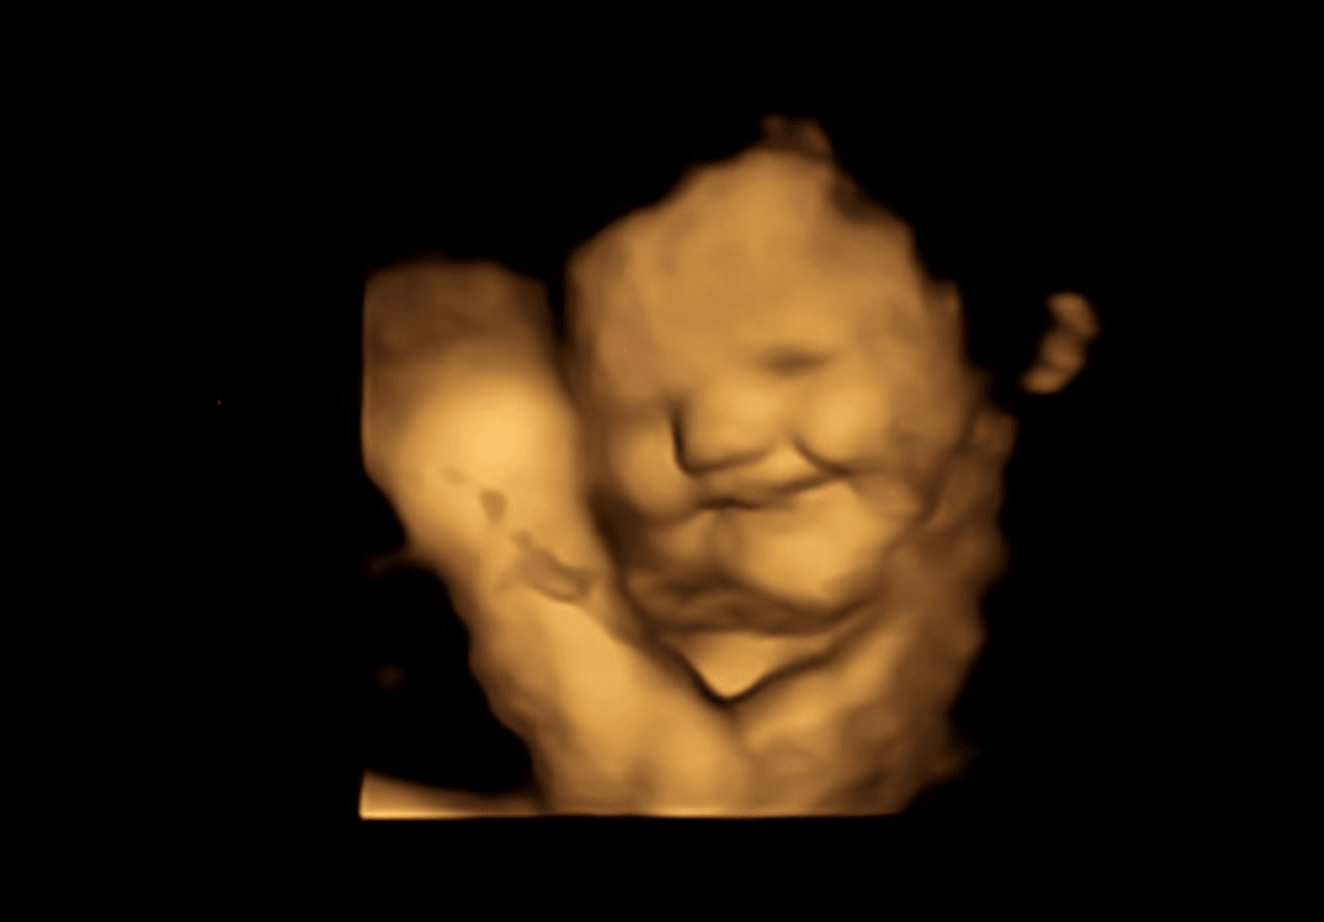

Naukowcy z Durham University przeprowadzili rutynowe badanie USG 4D matek w wieku 18-40 lat, zarówno w 32., jak i w 36. tygodniu ciąży. Uczeni obserwowali, jak mimika dziecka zmienia się w odpowiedzi na smaki marchwi i jarmużu (400 mg w postaci sproszkowanej w kapsułce). Matki nie jadły ani nie piły nic innego na godzinę przed badaniem USG, więc reakcja dziecka była właściwą reakcją na konkretne warzywo.

Mimika dzieci w obu grupach smakowych była uderzająca. Już niewielka ilość smaku marchewki lub jarmużu wystarczyła do wywołania reakcji (w porównaniu do grupy kontrolnej).